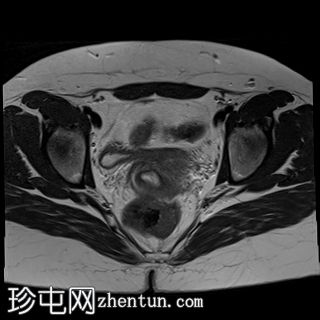

矢状位

T2加权像

双侧卵巢位置接近(卵巢相吻),左侧卵巢内可见一边界清晰的囊性病变,大小约3.1 × 2.7 × 2.9 cm,T1加权像呈高信号,T2加权像可见暗点征及内部暗点征。以上MRI特征符合卵巢子宫内膜异位囊肿的诊断。

右侧卵巢可见一囊肿,大小约为 2.8 × 2.0 × 2.2 cm,T1 加权像呈高信号,囊内可见液-液平面,提示囊内含有不同时期的出血性物质。由于对侧卵巢存在典型的子宫内膜异位囊肿,且该囊肿无强化,影像学表现强烈提示为另一子宫内膜异位囊肿。

子宫大小、轮廓及信号强度均正常,子宫内膜分区结构完整。未见局灶性肌层病变,子宫内膜厚度在正常范围内。

左侧盆腔可见少量游离液体。